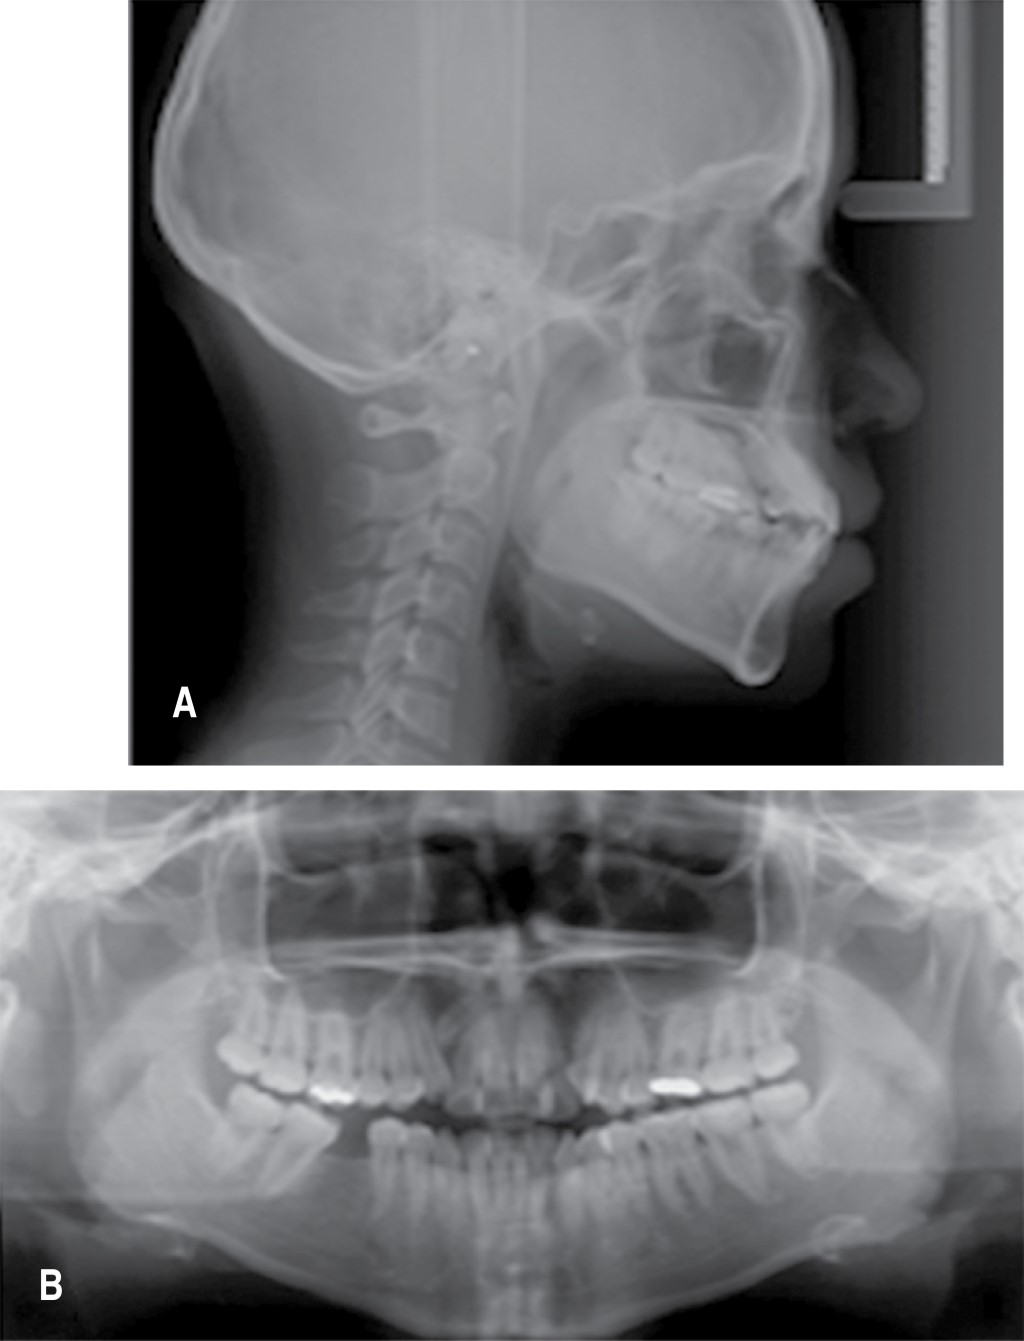

Paciente del sexo femenino de 21 años sistémicamente sana acude a consulta a la clínica de la Especialidad de Ortodoncia y Ortopedia Dentomaxilofacial de la Facultad de Estomatología de la Universidad Autónoma de San Luis Potosí. El motivo de la consulta mencionado por la paciente era: mejorar su sonrisa. Extraoralmente presentaba ligera asimetría facial, con labios prominentes. Al sonreír se observó una altura de sonrisa baja y compleja, la línea media superior se encontraba desviada 1.5 mm a la derecha y la inferior 1 mm a la izquierda (Figura 1A). Intraoralmente se identificaron restauraciones en ambos primeros molares superiores y la pérdida del primer molar inferior derecho, apiñamiento severo y las relaciones molares clase III izquierda y clase II derecha, con mordida borde a borde tanto horizontal como vertical (Figura 1B). Se tomaron radiografías laterales de cráneo y ortopantomografía (Figura 2).

El diagnóstico ortodóncico de la paciente consistió en una clase I esquelética con ANB de 1o con crecimiento neutro y biprotrusión dentaria debido a que las posiciones de sus dientes se encontraban alteradas con 1-PP (incisivo superior con respecto a su plano palatino) en 131o y 1-PM (incisivo inferior con respecto al plano mandibular) en 97o; un biotipo facial braquiocefálico y en tejidos blandos se identificó protrusión labial superior e inferior (Li/Ls con Sn-Pg) con 7 y 6 mm respectivamente.

Figura 2